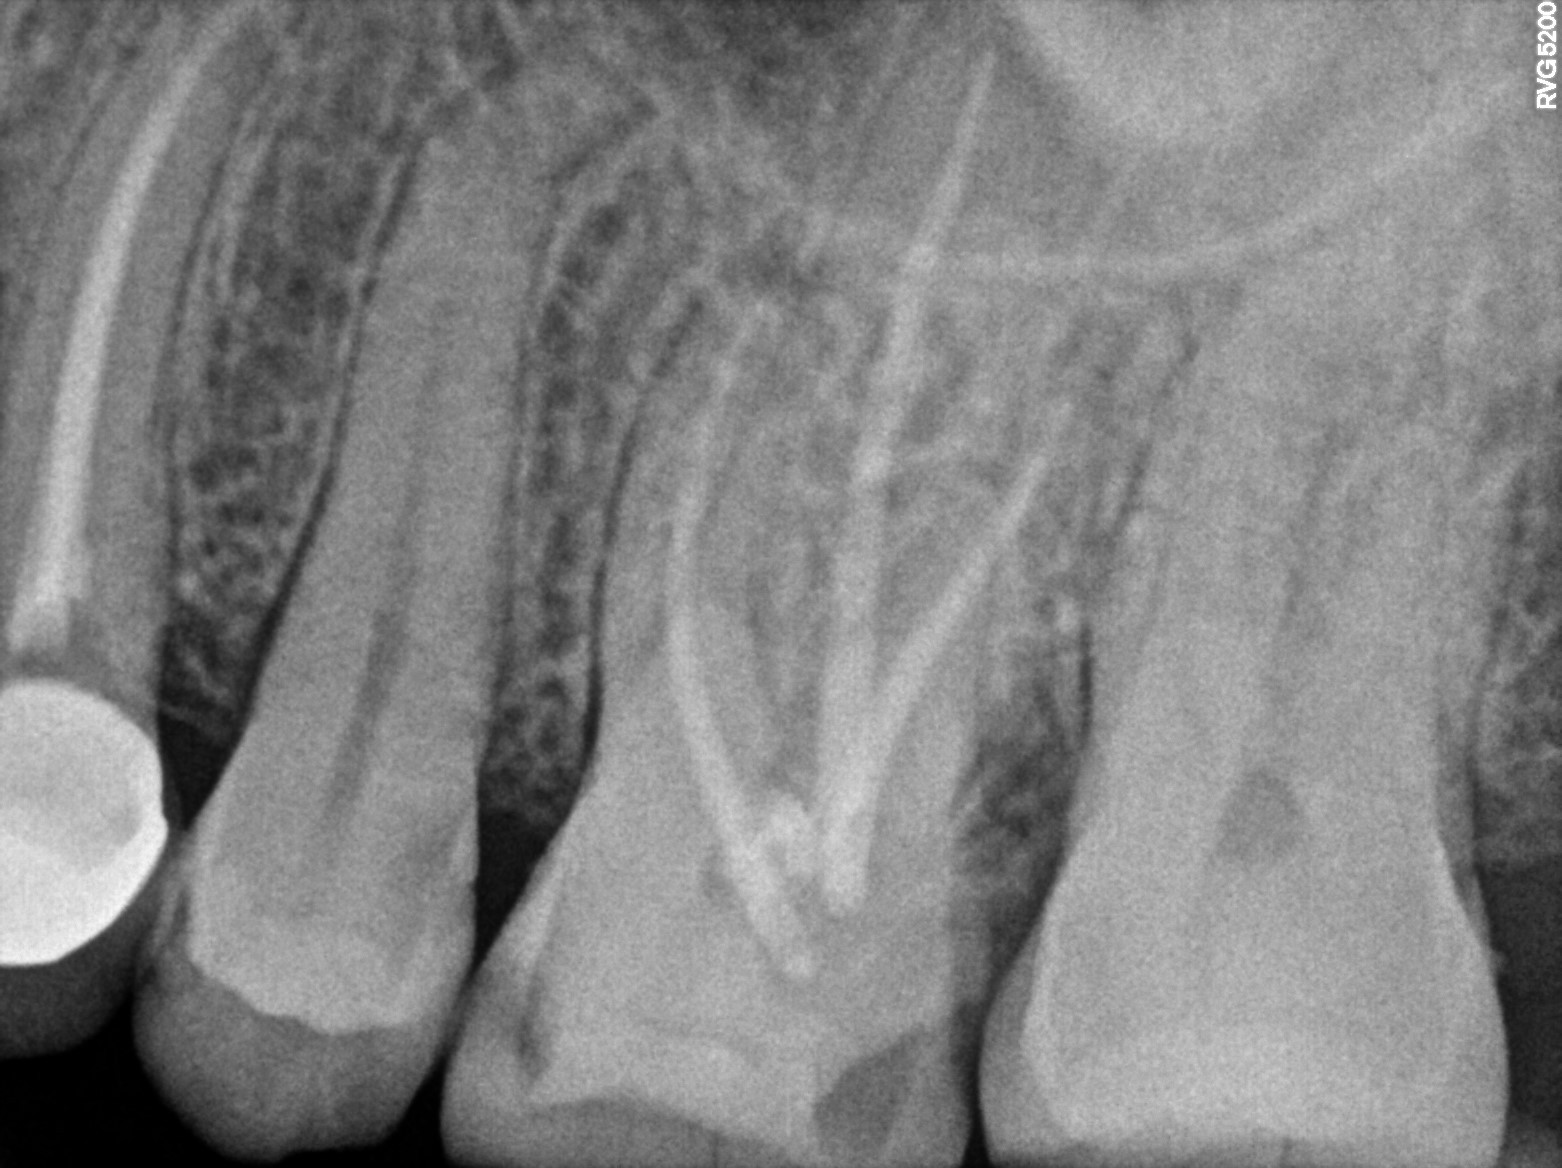

Dental Radiographs FHIR: DocumentReference · LOINC 24641-7

R55.jpg

24641-7